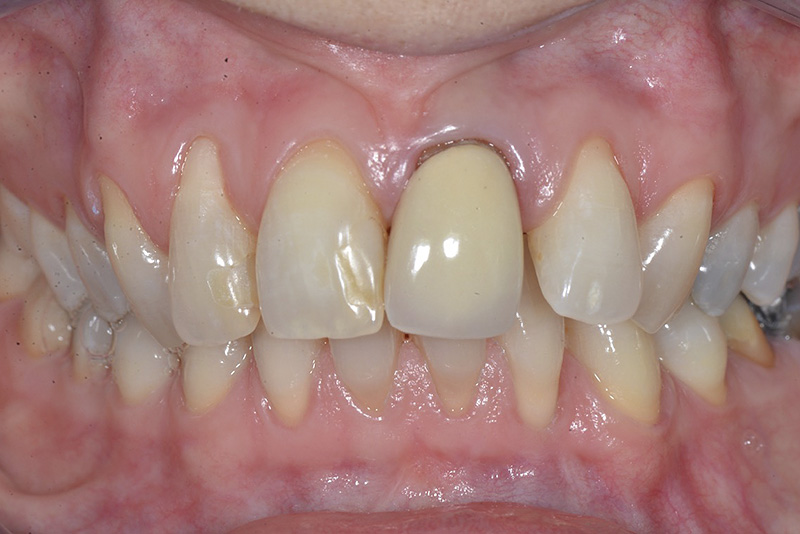

Vengono utilizzati 2 tipi di provvisori: il primo, cementato ai denti vicini, viene utilizzato dal momento dell’estrazione del dente fino ad impianto osteointegrato (circa 6 mesi); il secondo, avvitato direttamente all’impianto, ha una funzione di prova estetica ma soprattutto di guida per la maturazione dei tessuti gengivali peri-implantari portandoli verso la maturazione completa prima di posizionare la corona finale in disilicato di litio.